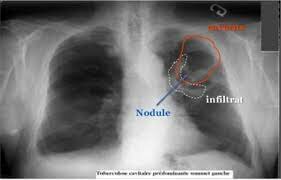

• tuberculose

tuberculose

Antiquité mais découvert par l'allemand dr Robert Koch la bactérie est la bacille de Koch